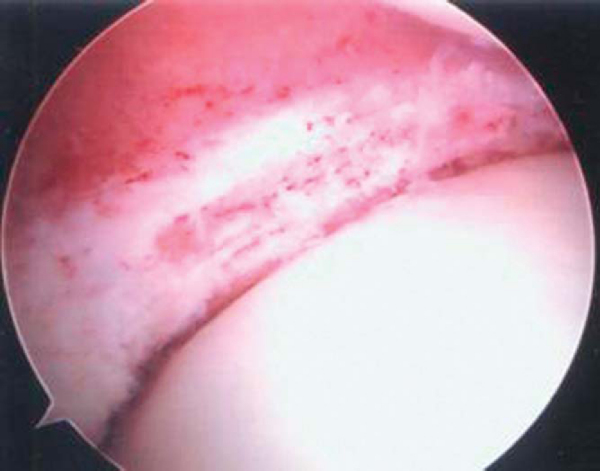

1. Arthroscopic Host Site Preparation

The initial arthroscopic portal should be established on the side opposite the graft, immediately adjacent to the patellar tendon border. This enables passage of the scope through the notch and visualization of the posterior horn attachment. Before the graft-side portal is made, a spinal needle is used to confirm that the portal site is directly in line with the horn attachments. Any obliquity in the skin incision to the horn attachments can cause difficulty in the proper orientation when the bone channel is prepared. Once the portals are made, the meniscal remnant is débrided to approximately a 2-mm vascular rim (Figs. 48-1 and 48-2 [1] [2]). The anterior portion of the meniscus can be addressed after the arthrotomy is made. To ensure proper channel height and alignment, a burr is used to remove the tibial spine to a height that is equal to the level of the tibial plateau articular cartilage and straight in line with the attachment sites. If there is still any difficulty in full visualization of the posterior horn attachment, a limited notchplasty should be performed. Likewise, the entire anterior attachment needs to be seen to be used as a reference for initial placement of the osteotome. Although a tourniquet can be inflated at any time, it is typically not done so until this point. By waiting, it allows confirmation of a vascular rim and conserves tourniquet time. Higher pressure and inflow rates are often needed to limit bleeding during bone channel preparation, which is why the tourniquet may be required at this point in the case.